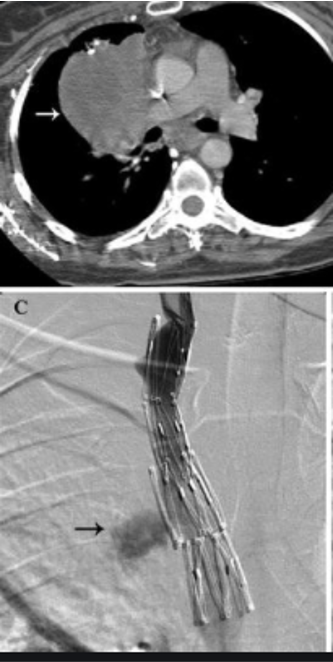

SVC syndrome may lead to dilated collaterals and edema –> airway compromise due to collateral vessels and swelling

treatment option = SVC stent placement